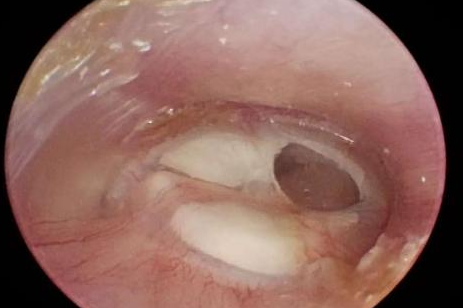

耳朵反复流脓、听力下降还有异味?当心,这可能是慢性化脓性中耳炎的症状。由于早期症状时好时坏,很多人觉得不是大问题,但拖延不治可能对听力造成不可逆的损伤。今天我们就来认清它的真面目,学会如何科学应对。 什么是“慢性化脓性中耳炎”? 慢性化脓性中耳炎,俗称“灌耳心”,典型症状包括耳内反复流脓(常为脓性分泌物,严重时可伴有臭味)、听力下降以及耳鸣等,部分患者还可能伴有眩晕。很多人是从小时候就开始出现症状,尤其是耳朵进水后容易急性发作或加重,成年后,听力持续减退往往成为主要困扰。 如果不及时治疗,炎症可能“向上”蔓延到颅内,引发脑膜炎、脑脓肿等危及生命的严重并发症。也可能侵犯面部神经或平衡器官,导致面瘫、持续眩晕或平衡障碍。最直接的后果是听力会不可逆地下降,严重时可能导致完全失聪。 “慢性化脓性中耳炎” 如何治疗? 慢性化脓性中耳炎的基础治疗需先用双氧水或生理盐水清洗耳道脓液,再滴入敏感抗生素耳液(如氧氟沙星滴耳液)。急性发作或重症时需口服或静脉注射抗生素并辅以抗炎药。若药物控制不佳或已有器质性病变,则需手术,包括乳突切除术清除病变组、鼓膜成形术修复穿孔鼓膜、听骨链重建术改善传音功能及胆脂瘤清除术清除胆脂等。 患者常见问题解答 问 手术后多久能恢复听力? 答 术后恢复情况与手术方式、个人身体情况有关。若为鼓膜修补手术,术后1—3个月左右,听力会逐渐改善,若进行听骨链重建手术,通常需要 3 到 6 个月,听力才能趋于稳定。术后需定期复查,监测听力恢复情况。 问 儿童患者能手术吗? 答 如果孩子的病情确实需要手术,家长不用太担心,儿童也是可以接受手术治疗的。医生会根据孩子的年龄大小、病情严重程度,选择最适合的手术方式,比如现在常用的微创技术,就能尽量减少手术对孩子耳朵的创伤,让孩子恢复的更好。 问 如何预防复发? 答 术后严格遵医嘱用药、复查,避免感冒及耳部进水,保持鼻腔通畅,减少咽鼓管阻塞。 贵州航天医院耳鼻咽喉科简介 张光进 中共党员,耳鼻咽喉科主任,副主任医师 临床擅长:对耳鼻喉头颈常见病的诊治具有丰富的临床经验,擅长鼻内镜、耳内镜、耳显微、头颈咽喉部肿瘤及眩晕手法复位等的诊疗。 曾先后前往第三军医大学西南医院、复旦大学耳鼻喉科医院、上海新华医院及北京友谊医院进修学习;遵义市医学会常务委员;主持及参与级科研课题2项,发表专业论文10余篇。 陈维信 九三学社社员,耳鼻咽喉科主任医师 临床擅长:对耳鼻咽喉科常见疾病的诊治具有丰富的临床经验,擅长耳、鼻、喉及头颈部位的手术。 曾先后前往上海交通大学附属仁济医院耳鼻喉-头颈外科、北京大学人民医院耳鼻喉-头颈外科参加鼻内镜外科进修学习。中国睡眠研究会委员,贵州省医学会耳鼻喉-头颈外科学分会委员,贵州省耳鼻喉-头颈外科学会理事,贵州省医学会变态反应学分会委员,贵州省防聋治聋技术指导组专家,遵义市耳鼻喉科分会副主任委员,遵义市医疗事故鉴定专家库成员;主持省部级科研课题2项,发表专业论文20余篇。 秦 晋 耳鼻咽喉科副主任医师 临床擅长:对耳鼻咽喉科常见疾病的诊治具有丰富的临床经验,擅长耳、鼻、喉及头颈部位的手术。 遵义市医学会常务委员;曾先后在第三军医大学西南医院、湖南湘雅鼻颅底培训班进修学习。 贵州航天医院耳鼻咽喉科简介 基本情况 贵州航天医院耳鼻咽喉科拥有一支经验丰富、技术精湛的医疗团队,共有医师9名,其中副高级以上专家5名,医学硕士2名,开放床位20张,拥有德国WOLF鼻窦内窥镜系统、日本奥林巴斯电子喉镜、奥林巴斯电子鼻咽镜、丹麦临床听力监测设备、声导抗仪、听觉诱发电位、耳声发射仪、美国杰西低温等离子治疗仪、杭州好克鼻窦内窥镜系统、鼻动力系统、耳显微镜、耳用电钻、微波治疗仪等设备。 专科特色 (一)耳部疾病 耳内镜下胆脂瘤切除术、III型鼓室成形术+人工听骨链重建术。 (二)鼻部疾病 内镜下鼻息肉切除术、鼻窦功能开放术。 (三)咽喉疾病 内镜下扁桃体、腺样体低温等离子切除术 (四)交叉学科 1.经鼻内镜下眶内肿瘤切除术 2.经鼻内镜下鼻腔泪囊吻合术 诊疗范围 (一)常见耳疾的诊断和治疗:中耳炎、耳聋、耳鸣等。通过各种耳科检查手段,如耳镜检查、听力测试和耳脑干听觉诱发电位检查等,准确诊断患者病情,制定个性化治疗方案。 (二)鼻炎、鼻窦炎、鼻出血等鼻科疾病的诊断和治疗:采用微创技术,如鼻内窥镜检查、低温等离子手术等,为患者提供有效的治疗方案。 (三)喉炎、声带息肉、声带白斑等喉科疾病的诊断和治疗:通过声带电子镜、喉镜等设备,准确判断患者的喉部病变,为患者提供精准的治疗方案。 (四)鼻眼、鼻颅底相关手术。